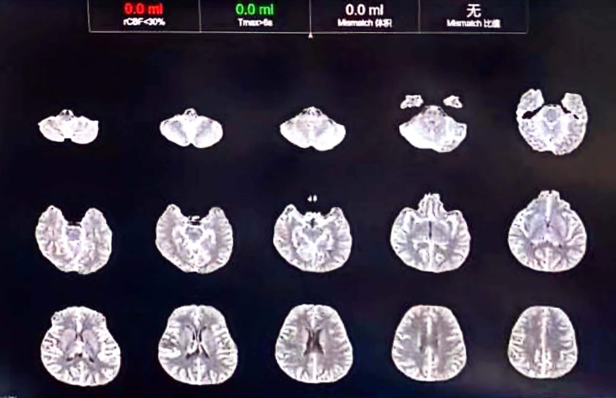

治疗后24小时CTP

OPTION研究是应用注射用重组TNK组织型纤溶酶原激活剂静脉溶栓治疗延长时间窗急性非大血管闭塞性卒中研究,它具有多中心、前瞻性、随机、开放标签、终点盲法研究,OPTION项目的技术方法、国内外的研究背景及创新性。目前对于发病4.5小时脑卒中的患者治疗,国内外都有成熟的指南共识;而对于4.5-24小时非大血管闭塞的脑卒中患者,目前国内外治疗的方法有限。随着影像技术的发展,目前可以识别卒中发作24小时内可挽救的缺血脑组织,而通过静脉溶栓实现再灌注有可能改善4.5-24小时内的临床预后。